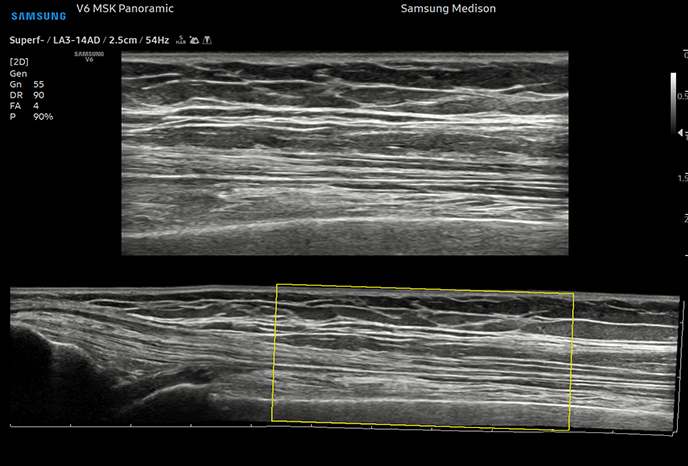

02최첨단 정밀 검사대학 병원급 하이앤드 초음파 장비와 다각적 검사 시스템

심장 질환 진단에서 가장 중요한 것은 ‘심장의 상태를 얼마나 정확하게 볼 수 있느냐’입니다. 저희 센터는 대학병원급 하이앤드 초음파 장비를 도입하여, 실시간 3D 렌더링으로 정밀 진단이 가능하며, 심장의 구조·혈류·기능을 실시간 고해상도로 관찰합니다.

미세한 판막 움직임, 혈류 속도 변화, 심방·심실 크기와 수축력까지 정밀하게 분석할 수 있어, 심장질환의 조기 발견과 치료 계획 수립에 큰 차이를 만듭니다.